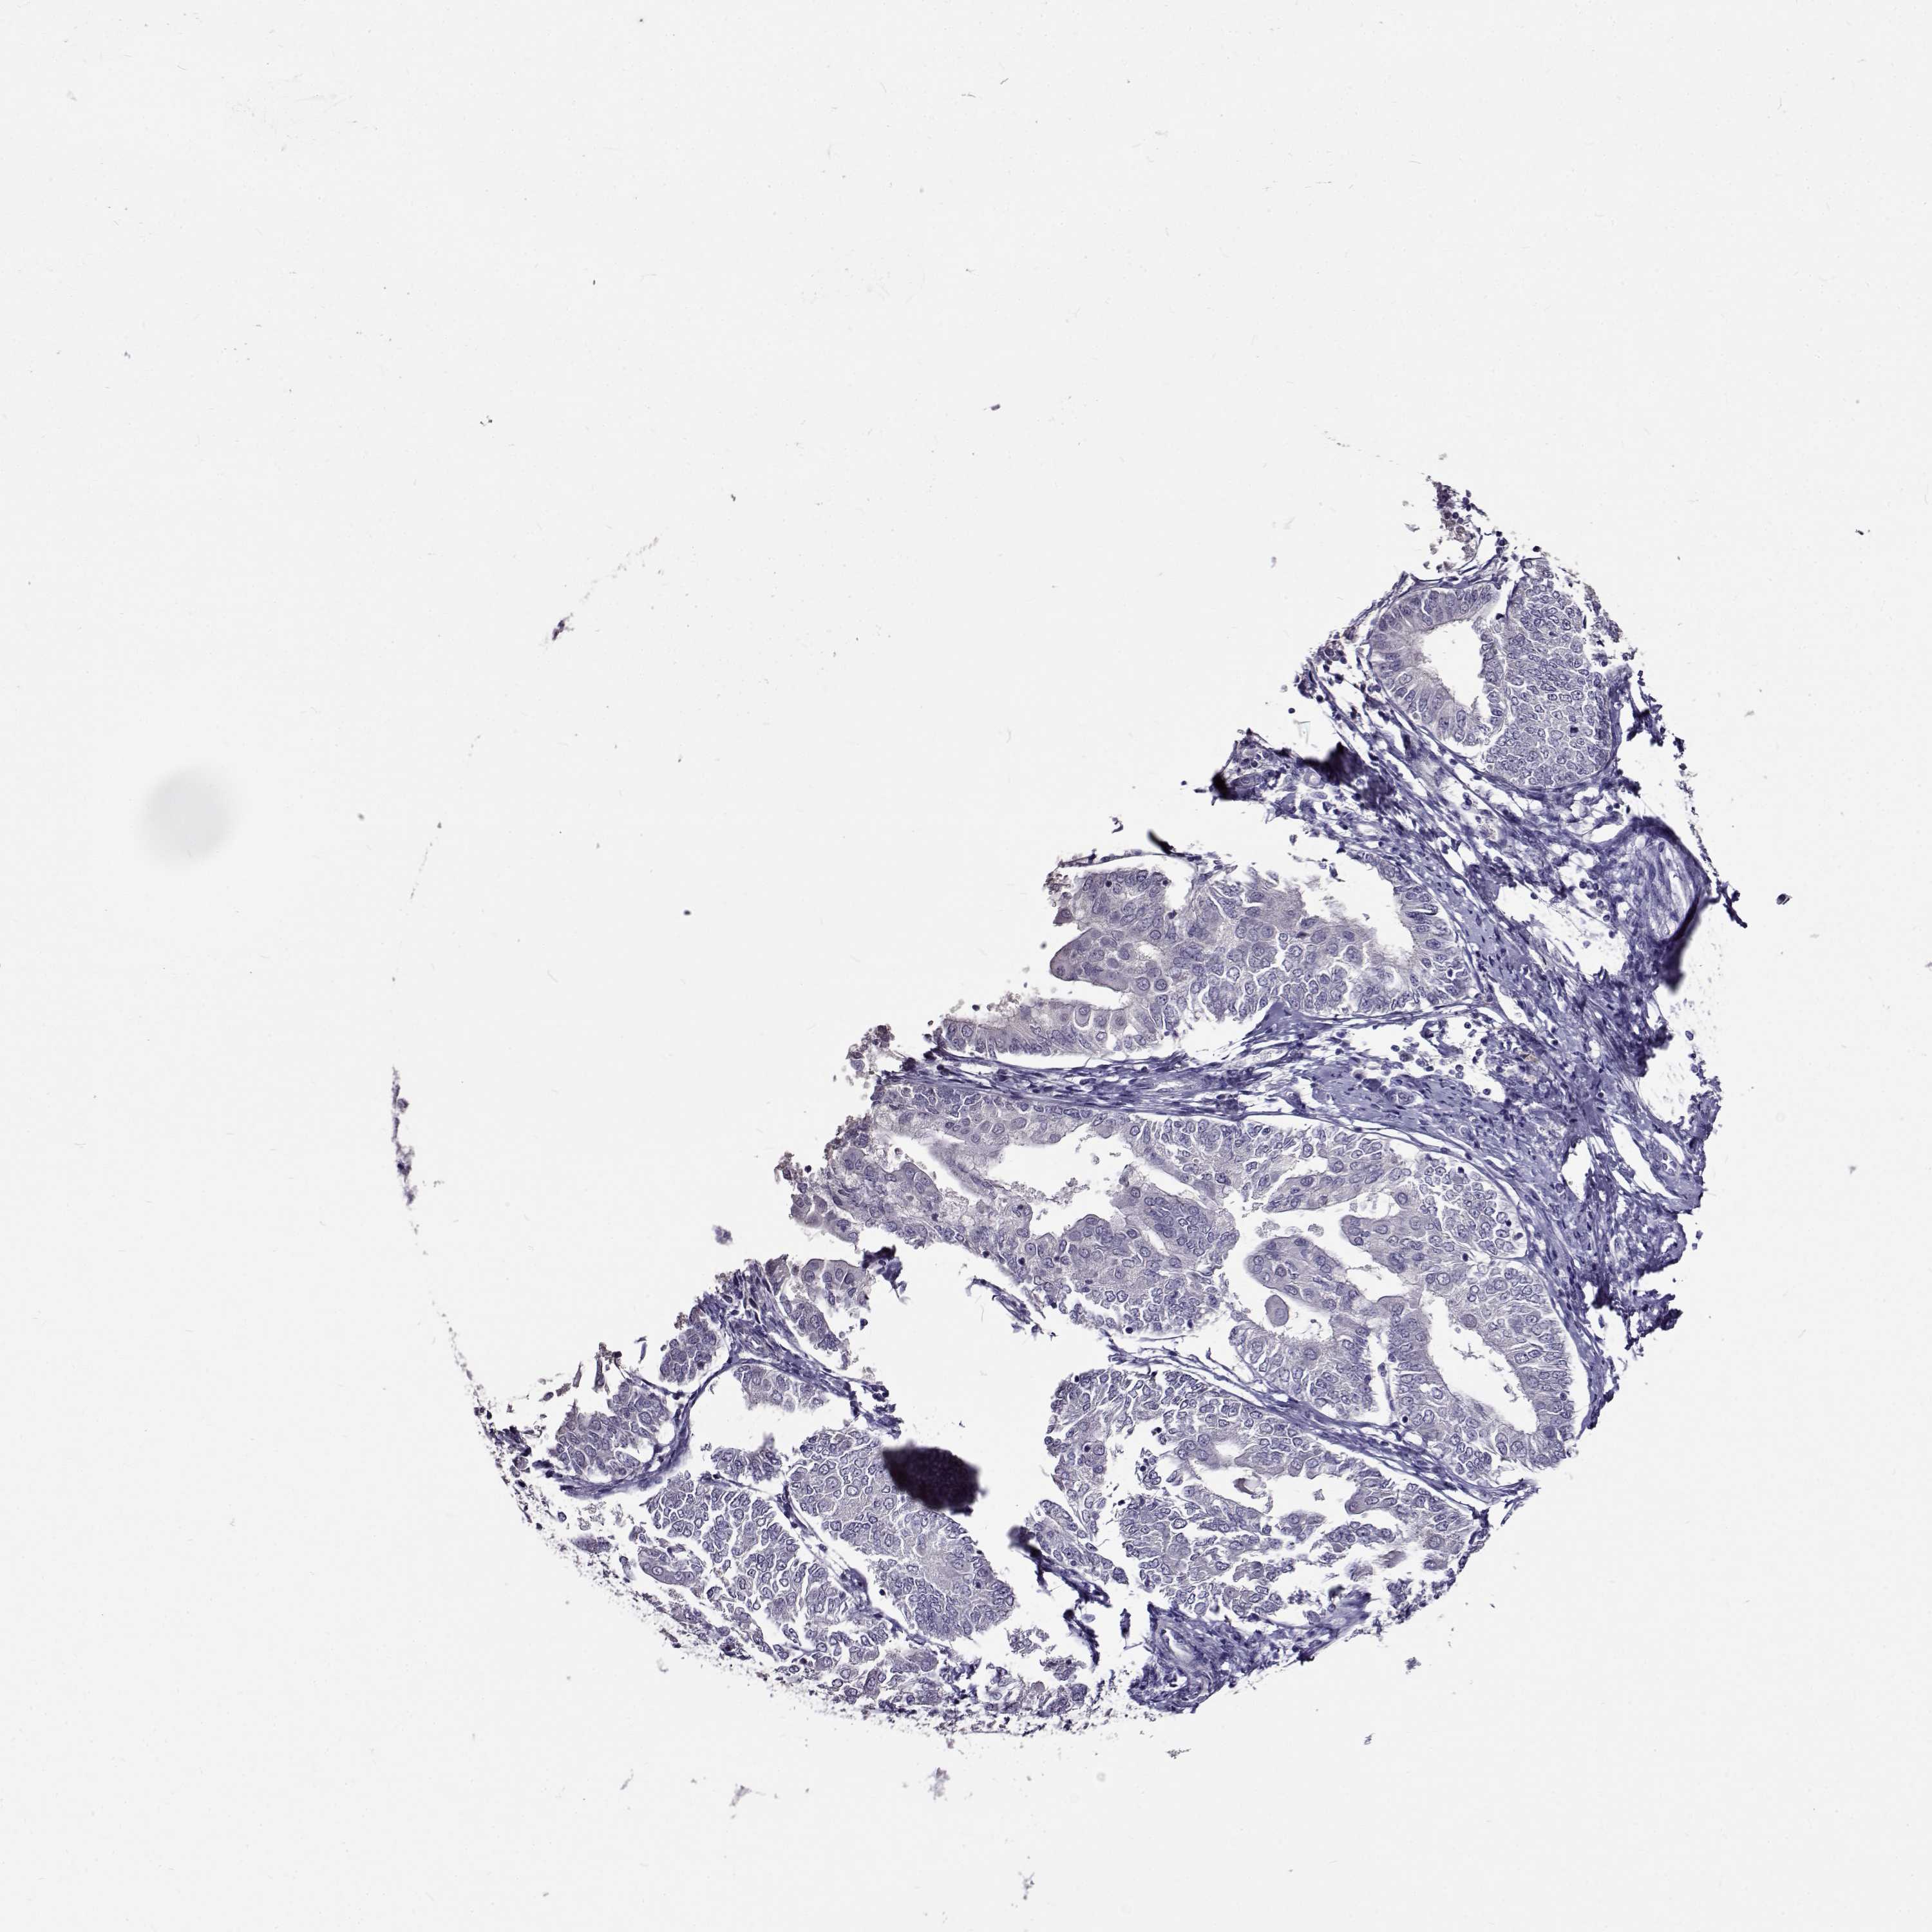

ENDOMETRIAL CANCER - Protein expressioni

A mouse-over function shows sample information and annotation data. Click on an image to view it in a full screen mode. Samples can be filtered based on level of antibody staining by selecting one or several of the following categories: high, medium, low and not detected. The assay and annotation is described here.

Note that samples used for immunohistochemistry by the Human Protein Atlas do not correspond to samples in the TCGA dataset.

Antibody stainingi

Antibody staining in the annotated cell types in the current human tissue is reported as not detected, low, medium, or high, based on conventional immunohistochemistry profiling in selected tissues. This score is based on the combination of the staining intensity and fraction of stained cells.

Each image is clickable and will lead to virtual microscopy that enables deeper exploration of all samples and also displays staining intensity scores, fraction scores and subcellular localization as well as patient and tissue information for each sample.

Antibody HPA020108

Antibody HPA029473

Antibody CAB016762

Staining

High

Medium

Low

Not detected

Intensity

Strong

Moderate

Weak

Negative

Quantity

>75%

75%-25%

<25%

None

Location

Nuclear

Cytoplasmic/membranous

Cytoplasmic/membranous,nuclear

Adenocarcinoma, NOS

Adenocarcinoma, metastatic, NOS

Carcinoma, NOS